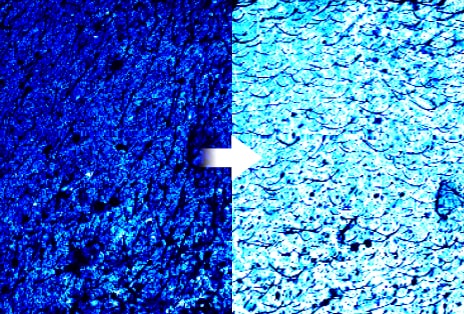

3) Excellent absorbency

-Skin Booster Boosting Mode in level 6 for 3 minutes

-Human application test results: Use of TOXNFILL Hyaluronic Boosting Ampoule / Comparison between two control groups, Skin Booster + Cosmetics vs. Hand + Cosmetics /

After absorption of the ampoule and a 30-minute wait, the degree of absorption, absorption amount, absorption depth, and absorption speed of the ampoule were measured using Raman microscopy, and the improvement rate compared to the Hand + Cosmetics control group was expressed in a %.

-February 5 - February 16, 2024 / 20 adult women (including 10 with sensitive skin) / P&K Skin Clinical Research Center

-Test results have been excerpted from the test performance report for consumer understanding.

-There may be personal differences depending on individual skin characteristics or skincare product combinations.